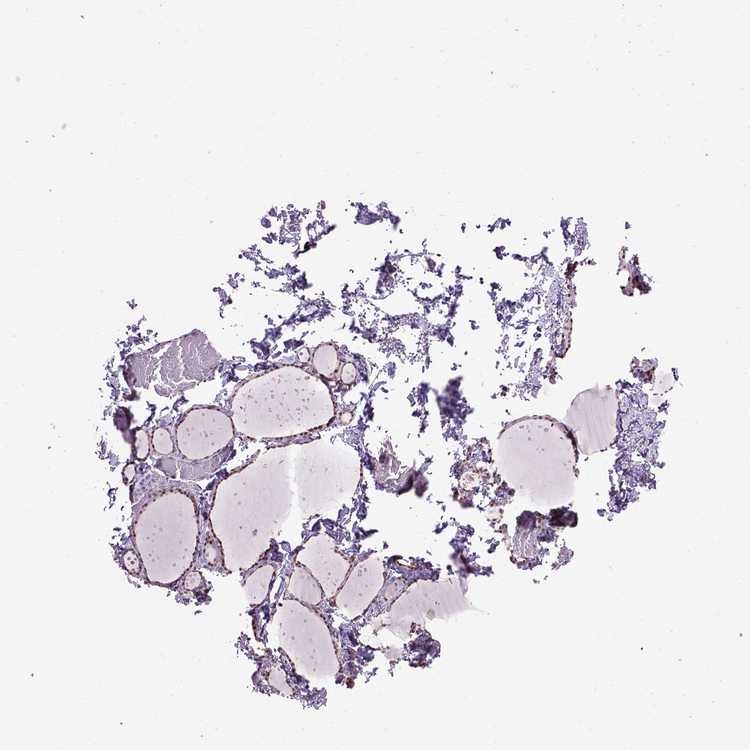

THYROID GLAND - Antibody stainingi

Antibody staining in the annotated cell types in the current human tissue is reported as not detected, low, medium, or high, based on conventional immunohistochemistry profiling in selected tissues. This score is based on the combination of the staining intensity and fraction of stained cells.

Each image is clickable and will lead to virtual microscopy that enables deeper exploration of all samples and also displays staining intensity scores, fraction scores and subcellular localization as well as patient and tissue information for each sample.

Antibody HPA019730

Glandular cells High